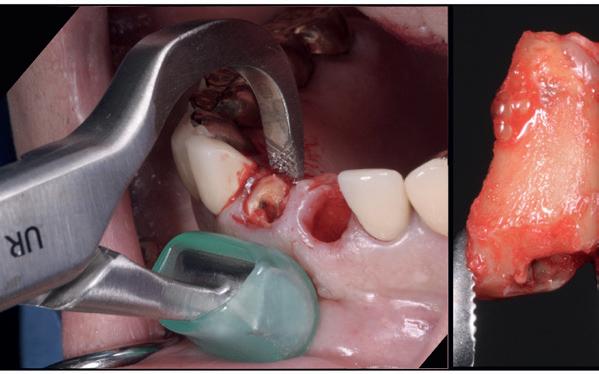

1. Afgebroken 24. Geen hoektandgeleiding aanwezig.

2. Decapiteren van het element en splitsen van de wortels.

3. Verwijderen van de radices.

4. Curettage en spoelen met een zoutoplossing.

5. Het ridge preservation protocol waarbij we proberen zoveel moge-

lijk bot te behouden met behulp van een xenograft.

6. De tijdelijke pontic, waarbij gebruikgemaakt wordt van de eigen afgebroken kroon en wat composiet. 7-10. Een full thickness flap osteotomie met hand plaatsing van een MegaGen AnyRidge Implantaat volgens protocol resulteerde in een

De implantaatplaatsing en de beslissende fout (afbeelding 1-13)

De extractie verliep voorspoedig, waarbij ik zoals al-

tijd probeerde de buccale botlamel intact te houden. Dit is cruciaal voor latere botbehoud en implantaatplaatsing. Na curettage en spoelen van de alveole beoordeelde ik de situatie opnieuw: de botcondities leken gunstig voor een immediaat implantaat.

Hier begon echter de cruciale fout in mijn klinisch besluitvormingsproces. In mijn streven naar maximale primaire stabiliteit - wetende dat immediaat belasten enkel mogelijk is bij hoge stabiliteit -on-

derprepareerde ik de osteotomie. Dit betekende dat ik een iets te smal implantaatbed creëerde, in de hoop dat het implantaat stevig in het bot verankerd zou worden.

Op papier leek dit een logische stap: het MegaGen AnyRidge-implantaat dat ik koos, gaf me een stabiliteit van 60Ncm—een cijfer dat vertrouwen gaf in immediaat belasten. Maar in mijn enthousiasme had ik onvoldoende rekening gehouden met de biologische gevolgen van overmatige compressie.

Door de te hoge druk op het omringende bot verminderde daarin de doorbloeding, wat leidde tot een verhoogd risico op botnecrose. Dit was geen fout van abutmentkeuze of occlusie; dit was puur het gevolg van mijn drang naar optimale stabiliteit en de wens om het implantaat direct te belasten, onder invloed van patiëntdruk.